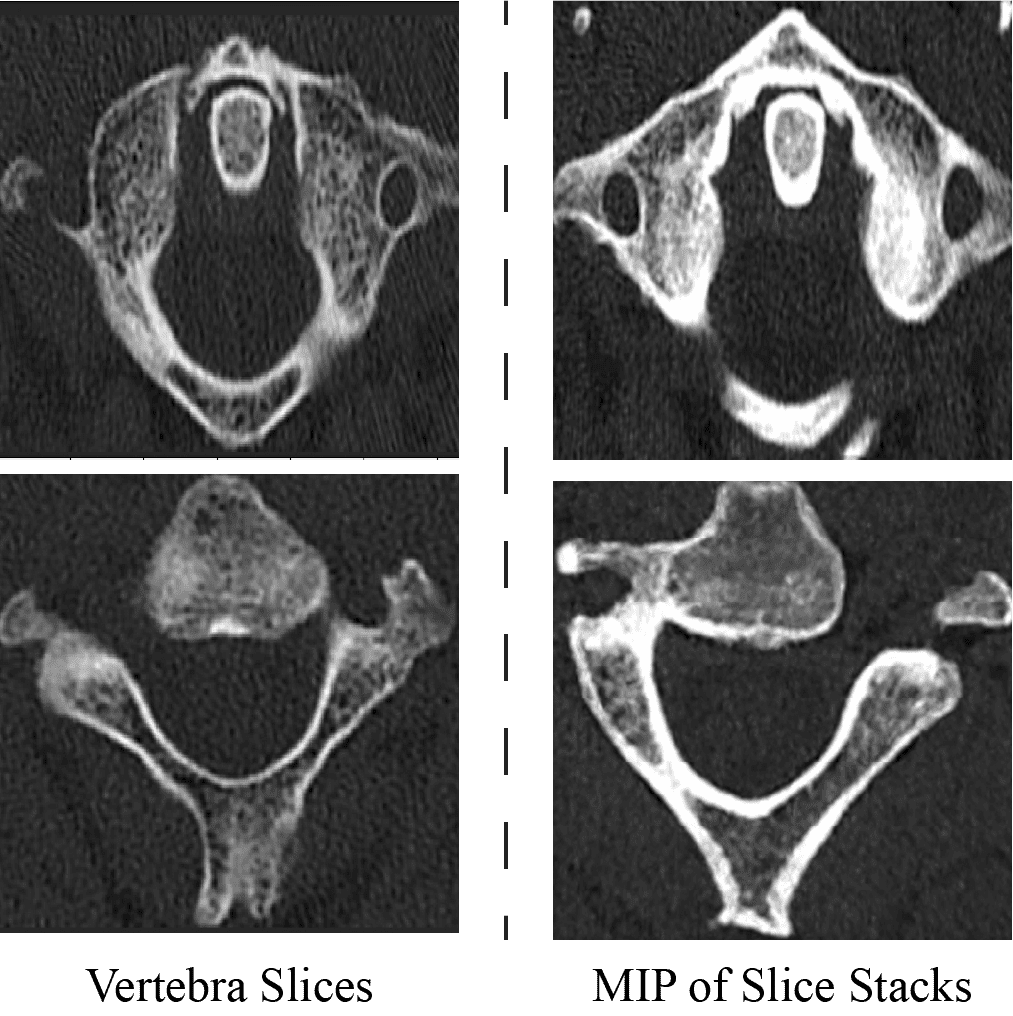

This approach focused on leveraging spatio-sequential information within CT volumes for robust fracture classification. Unlike projection-based methods that relied on isolated 2D views, our 2.5D framework captured volumetric context by processing sequences of anatomical data. We investigated two distinct variations of this spatio-temporal approach to optimize the trade-off between contextual depth and computational efficiency. The first utilized direct volumetric slice stacks to capture immediate 3D context, while the second expanded the receptive field by employing stacks of MIPs. In both configurations, the networks predicted fracture probabilities at the sequence step level, with the final vertebra diagnosis determined via majority voting. At the patient level, we evaluated two strategies: a standard ”if-any” criterion, where a patient was flagged if any vertebra was fractured, and an adaptive threshold-based method utilizing score-level fusion to maximize model agreement.

The preprocessing pipeline for the 2.5D spatio-sequential approach was designed to overcome the limitations of single-slice analysis by incorporating volumetric context through specific stacking techniques. A bone windowing technique (width: 400 HU, level: 1400 HU) was first applied to the CT volumes to enhance the contrast of vertebral structures. To provide the network with richer spatial information, we utilized a slice-stacking strategy rather than processing isolated 2D images. For the standard approach, 15 evenly spaced slices were extracted from each vertebra VOI. Each selected slice was then augmented by stacking its two preceding and two succeeding slices along the channel axis, forming a 5-slice input stack. This configuration allowed the model to leverage local 3D spatial relationships, effectively mitigating the ambiguities often found when relying solely on individual slices.

We also investigated an alternative method aimed at expanding the anatomical context without excessively increasing the model’s input dimensionality. In this variation, we extracted 75 equally spaced slices from the vertebra and formed mini-stacks of five consecutive slices (central slice ± 2). We then computed the Maximum Intensity Projection (MIP) for each mini-stack. These resulting projections were subsequently grouped into 15 sequential sets, creating stacks of projections rather than raw slices. This technique effectively increased the volumetric coverage available to the model while maintaining efficient processing dimensions. In both approaches, all input stacks were resized to 256 × 256 × 5 to ensure uniformity for training. A visual example of the data is given in Supplementary Figure S10.